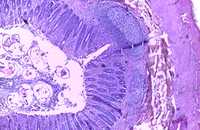

Onze appendix heeft wél een functie!

In tegenstelling tot wat we lang geloofden, heeft de appendix wel degelijk een functie!

In onze darmen zitten heel wat bacteriën, die belangrijk zijn voor onze gezondheid. De appendix bewaart een 'back-up' van al die goede bacteriën.